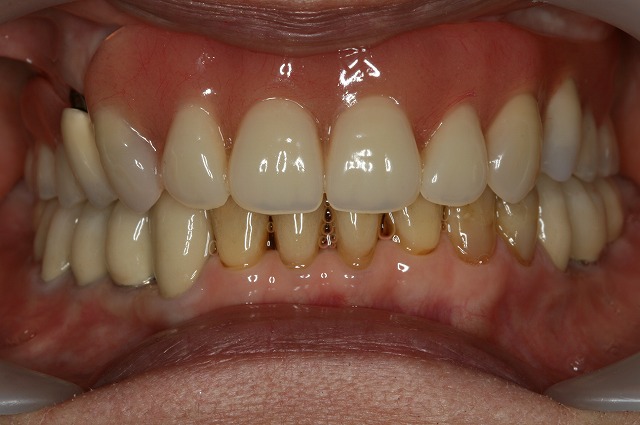

CASE03

Before

After

| 主訴 |

前医に上顎の歯を全て削られほぼほぼ連結され最初は良かったが1年ほどで脱離を繰り返すようになる別の医院に行ってもこれは前医にと言われてたらい回し。誰も治せない状態で当院もつけてくださいと来られました。 |

| 施術内容 |

インプラント…下顎4本・上顎6本 /

GBL(L)…1部位 /

ソケットリフト…2部位 /

GBR(S)…4部位 /

FGG…4部位 /

ジルコニア…11本 /

メタルボンド(インプラントポンティック部)…3本 |

| 治療期間 |

3年(50回) |